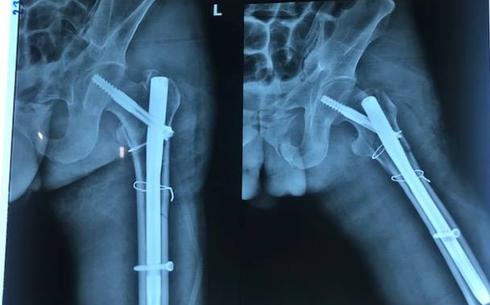

Bệnh nhân được mổ đặt nhiều dụng cụ ở các chấn thương. (Ảnh bệnh viện cung cấp) |

Kết quả cận lâm sàng xác định bệnh nhân bị đa chấn thương rất nặng như gãy xương gò má, gãy phức tạp đầu trên xương đùi trái, gãy xương chày chân, gãy nhiều mảnh đốt sống và có mảnh chèn vào tủy sống gây yếu một phần hai chân cũng như làm bí tiểu. Bệnh nhân được theo dõi vỡ gan, liệt ruột cơ năng, chấn thương phần khung chậu...

3 kíp mổ đã hoạt động liên tục trong gần 5 giờ để xử lý các chấn thương phần hàm mặt, cột sống, các gãy xương và bó bột. Anh Hiền được mổ giải ép, hàn liên đốt sống và đặt dụng cụ cột sống, phẫu thuật kết hợp xương đùi, kết hợp xương gót và bó bột cẳng chân, phẫu thuật nắn chỉnh xương gãy gò má, cung tiếp.